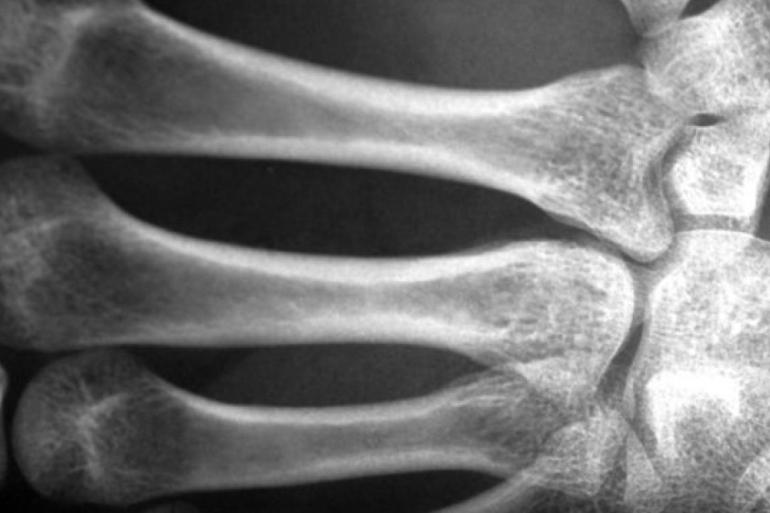

توصلت دراسة جديدة إلى وجود صلة مقلقة بين ارتفاع مستويات تلوث الهواء وهشاشة العظام.

وباستخدام عناوين المنازل لتقدير كميات أكسيد النيتريك وثاني أكسيد النيتروجين وثاني أكسيد الكبريت وجسيمات PM10 ، وجد الباحثون أنه مع ارتفاع التلوث، انخفضت كثافة المعادن في العظام في جميع أنحاء الجسم، بما في ذلك الرقبة والعمود الفقري والورك.

وسلطت الدراسة الضوء على العلاقة بين النيتروجين والعمود الفقري، وارتبطت زيادة بنسبة 10 في المئة من هذا النوع من التلوث على مدى ثلاث سنوات بمتوسط خسارة سنوية بنسبة 1.22 في المئة في كثافة المعادن في عظام العمود الفقري، أي ضعف الكمية التي تسببها الشيخوخة الطبيعية.